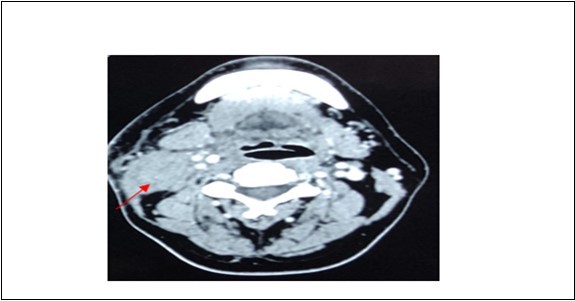

A 42-year-old gentleman, ex-smoker with underlying diabetes mellitus came to our clinic for right neck swelling for about 10 months. The swelling was gradually increasing in size and was giving occasional pain to the patient. But, there were no obstructive symptoms nor a history of prior exposure to radiation. Upon examination, there was a 2x2cm firm, fixed and non-tender swelling palpable at level II of right neck, with no skin changes seen. The facial nerve was intact and the oral cavity was clear. Proceed with flexible scope, there was no mass seen, and laryngeal structures were normal. Fine needle aspiration revealed normal salivary gland elements. A contrasted-CT scan reported a deep lobe parotid gland mass with non-opacification of the right internal jugular vein which could be from compression or thrombosis. [Figure 3] A wedge biopsy was performed subsequently which reported as squamous cell carcinoma, moderately-differentiated. [Figure 4, Figure 5 & Figure 6] Given the malignancy reported, a right total parotidectomy with right selective neck dissection was performed. Post-operatively, the patient developed House-Brackmann grade II facial nerve palsy. Histopathology showed evidence of squamous cell carcinoma with no involvement of adjacent nodes. A final diagnosis of T3N0M0 squamous cell carcinoma of the parotid gland was established. The patient was then referred to the oncology team for chemoradiation. Currently, the patient has completed adjuvant radiotherapy with no signs of recurrence observed so far at six months follow-up.

Figure 3.Contrasted CT neck showing mass at deep lobe of right parotid gland

Contrasted CT neck showing mass at deep lobe of right parotid gland